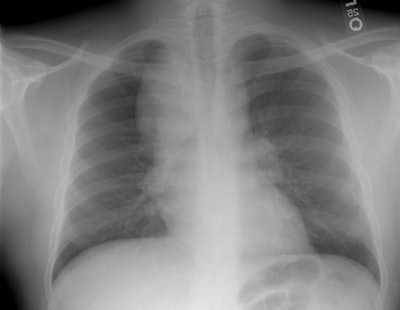

Hodgkins lymphoma developing in a patient with sarcoid:

The film below was from 1997. The right paratracheal mass has enlarged markedly in comparison to the patients old film. This finding was felt to be atypical for sarcoid and a CT was performed. The CT scan demonstrated a large anterior mediastinal/right paratracheal mass which severely compressed the superior vena cava, coupled with mediastinal and subcarinal adenopathy. (Click here to view CT scan). Mediastinoscopy was performed and the patient was discovered to have Hodgkins lymphoma.